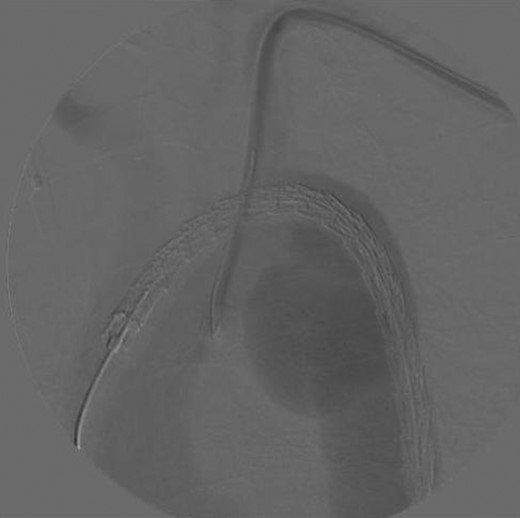

A 74-year-old woman was referred to our vascular service with a 6-month history of hoarseness of voice and intermittent dry cough. The patient’s medical history included hypertension and gastroesophageal reflux disease. Flexible laryngoscopy demonstrated a foreshortened, lateralised and flaccid vocal fold consistent with unilateral vocal cord paralysis. Subsequent computed tomography (CT) imaging of the neck and thorax revealed a saccular aneurysm in the aortopulmonary window measuring 39 mm (Fig. 1). Digital subtraction angiography confirmed the presence of a ductal aneurysm with a well-defined neck and no intraluminal thrombus (Fig. 2). There was no contrast extravasation into the mediastinum or pulmonary circulation. Following a cardiovascular multidisciplinary meeting, treatment options were discussed with the patient and consensus favoured endovascular repair. The distance from the proximal margin of the aneurysmal neck to the origin of the left subclavian artery measured just under 2 cm and therefore did not meet the manufacturer’s minimal landing zone requirements. To circumnavigate this dilemma, a left subclavian stent graft was inserted with its proximal end parallel to the main thoracic endoprosthesis. The procedure was uncomplicated and repeat imaging revealed widely patent stent grafts with satisfactory positioning and absence of endoleak (Fig. 3). Our patient was discharged home on the second postoperative day. She continued speech and language therapy postoperatively and has made remarkable recovery of phonation, declining any further treatment options for same.

Digital subtraction angiogram demonstrating the chimney-graft approach. Image acquired shortly before simultaneous subclavian and thoracic stent-graft deployment.